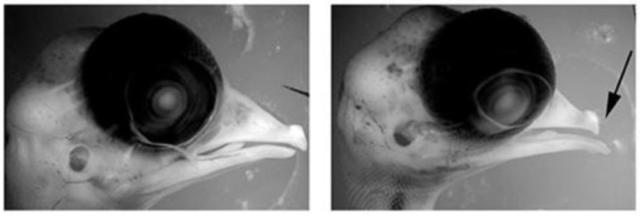

高温导致鸡胎出现了严重的颅面部畸形。与左边正常的胚胎相比,高温严重缩短了鸡胚胎的上喙(右)。图片来源:参考文献[4]

在进一步的研究中,科学家发现,神经嵴上有两个与温度相关的离子通道:TRPV1和TRPV4。它们在神经嵴向心脏和颌面部分化时起着非常重要的作用[4]。研究者用发育模式和人类相似的鸡胚做实验,结果发现:与在适宜环境中正常发育的鸡胚相比,在40~41℃的环境中暴露过一小时后再孵化的鸡胚,喙发育缺陷和心血管缺陷都有明显的增加。同时,研究者们还设计了诸如高温下抑制TRPV1和TRPV4、常温下激活TRPV1和TRPV4的动物实验作为对照,证实了这两个离子通道在高温致畸机制中的重要地位。